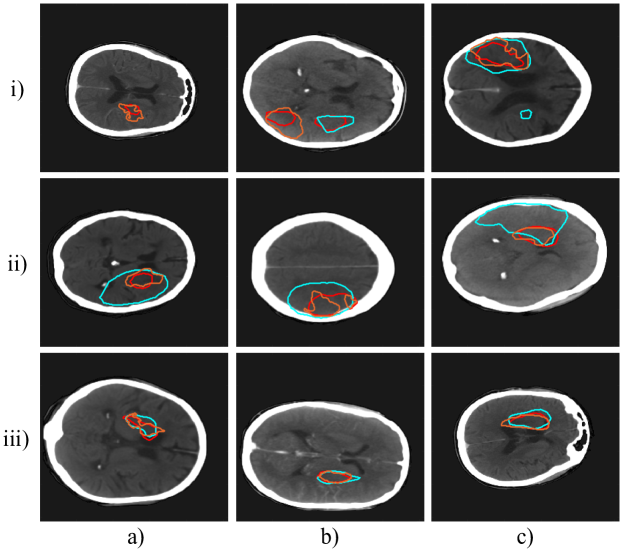

The 3D networks performed poorly. We observed that their increased number of parameters resulted in more overfitting. Additionally, they were unable to take full advantage of the third image dimension, due to the large number of scans with only 2 axial slices. For the two best models, the 2D U-Net and pre-trained PSPNet, we observe the focal loss improved model performance. We demonstrate in Fig. 4 that the focal loss predicted more fine details in the lesions that were missed by cross entropy in the pre-trained PSPNet. The cross entropy loss network often over-predicted larger lesions than the focal loss network, and the focal loss network was able to more closely predict the fine appearance features of the lesions, and predict areas that cross entropy completely missed.